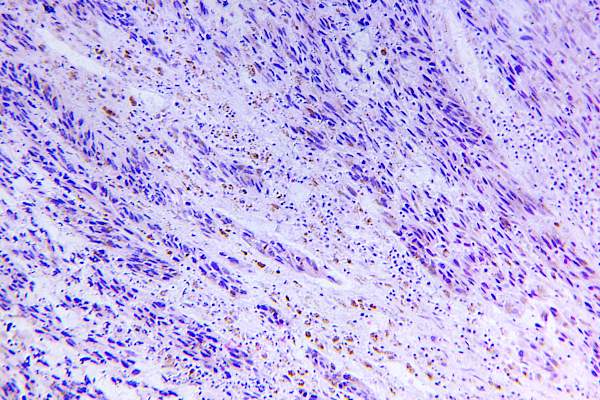

Fathi博士说:“分期是我们谈论黑色素瘤扩散的一种方式。”分期是由几个因素决定的,但最主要的是癌症的发展程度和是否转移。“1 - 3期是由皮肤癌在显微镜下的样子决定的。他说:“我们会寻找一些特征,比如癌症穿透了多少毫米,显微镜下是否有溃疡,以及是否有大量细胞正在分裂。”在第四阶段,癌细胞已经扩散到身体的远处区域、淋巴结或器官。